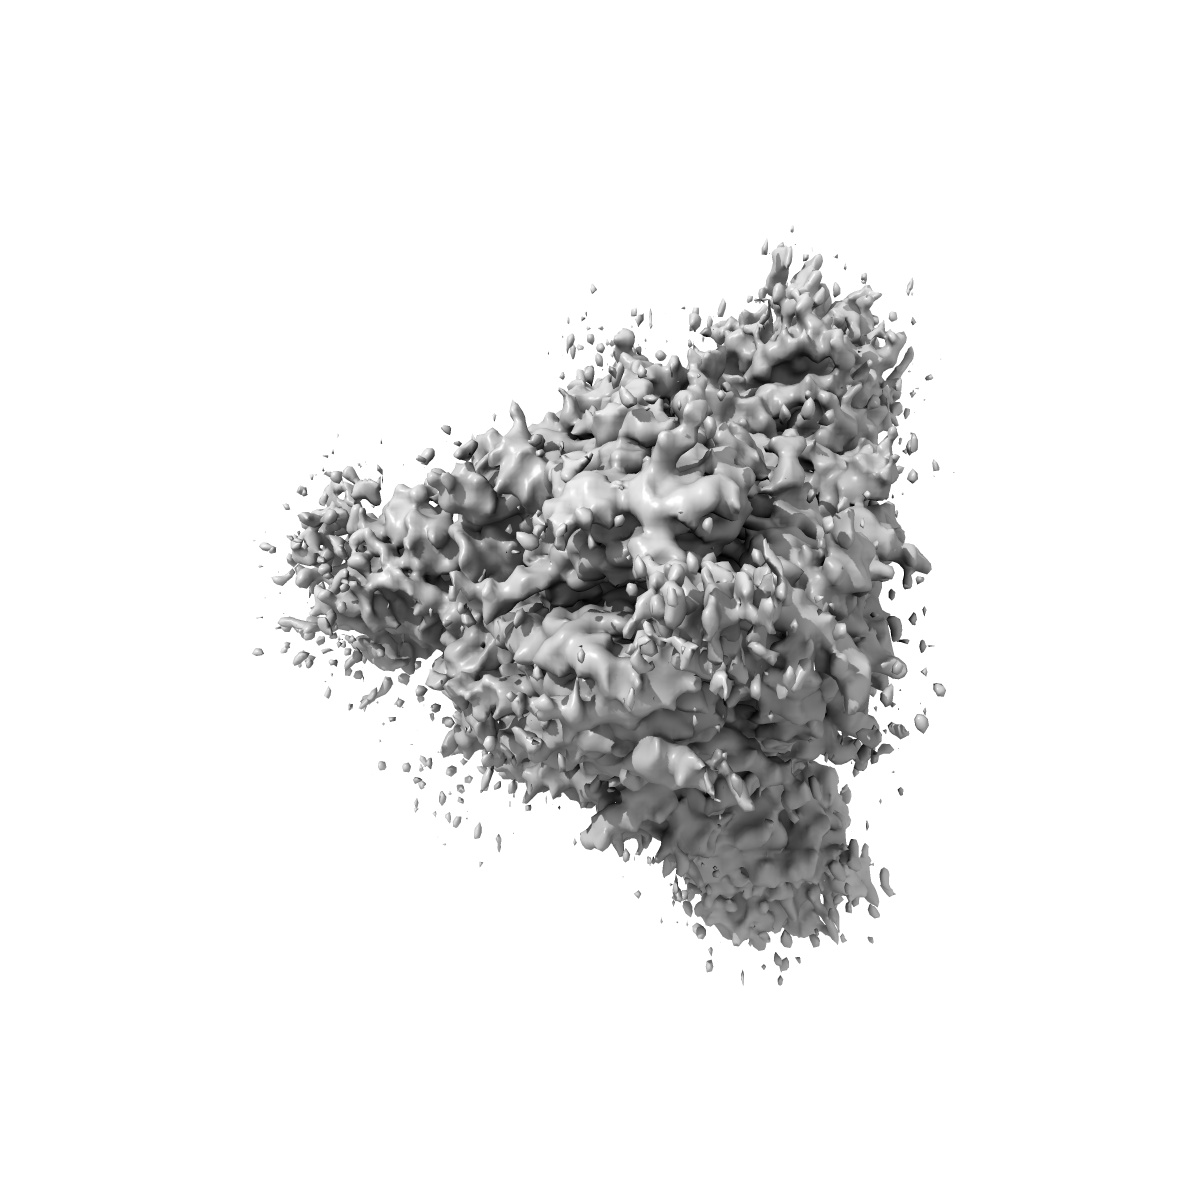

Cryo-EM structure of mink variant Y453F trimeric spike protein bound to one mink ACE2 receptors at downRBD conformation

Sample: Cryo-EM structure of mink variant Y453F trimeric spike protein bound to one mink ACE2 receptors at downRBD conformation